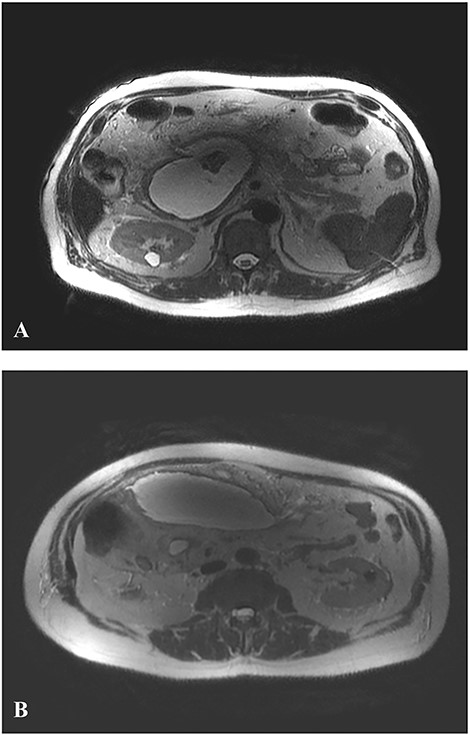

Upper abdominal magnetic resonance imaging, magnetic resonance cholangiopancreatography (Fig. 1) and contrast-enhanced computed tomography (CT) (Fig. 2) revealed large walled-off pancreatic necrosis in the pancreatic head, measuring 10.5 × 6.5 × 9 cm, compressing the inferior vena cava, the common bile duct and the duodenum. There were also peripancreatic pseudocysts, with the biggest measuring at 12.5 cm.

Axial T2-weighted MR image. A. WOPN: large pancreatic collection with hyperintense fluid and hypointense non-liquefied components (debris) pressing inferior vena cava. B. Peripancreatic pseudocysts.